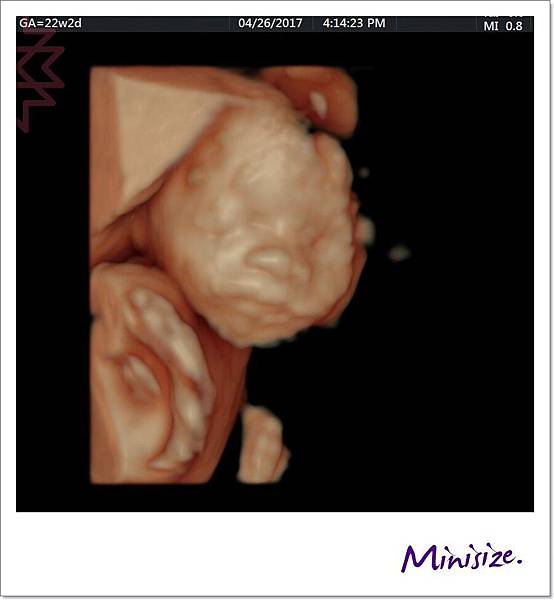

面

一直很期待看到寶寶的長相

究竟是像爸爸還是麻麻?!

爸媽綜合體又會呈現什麼樣子

也許寶寶想保留一點神祕感

這是唯一張好好配合拍照的

大大的鼻子、嘴巴好福氣!!

還記得前面提到 會有兩次醫療人員操作儀器檢查嗎?

技術師只捕捉到一張寶寶正面照

其他因寶寶姿勢的關係

技術師交棒給醫生的時候也有特別註明

醫生快速地全項目檢查一輪後

將之前未完成的部分也足一補齊

我們又再度回到胎兒的正臉

此時寶寶跟我們玩起遊戲來了

頑皮寶寶:手手、 臍帶 一起遮住臉臉不給你們看